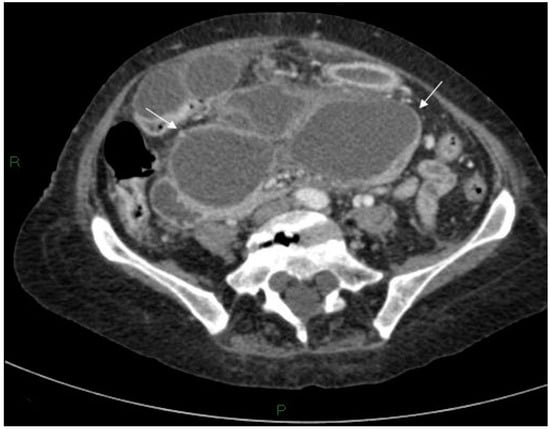

On day six her clinical condition deteriorated, she was pyrexial and haemodynamically unstable. The patient complained of increased abdominal pain and had a raised white cell count and a raised arterial lactate level. An erect chest x-ray revealed free air under the right hemidiaphragm. Following initial resuscitation and administration of antibiotics, a CT was performed revealing the known pseudocyst with anterior compression of the stomach, free fluid in the abdomen and considerable free intra-abdominal air (Figure 3, Figure 4 and Figure 5).

Figure 5.

Initially, Axial CT scan showing the stomach containing a nasogastric tube anterior to the cyst (large white arrow), free air (small white arrows) and inflammatory changes in the soft tissues between the stomach/duodenum and the cyst (black arrow).